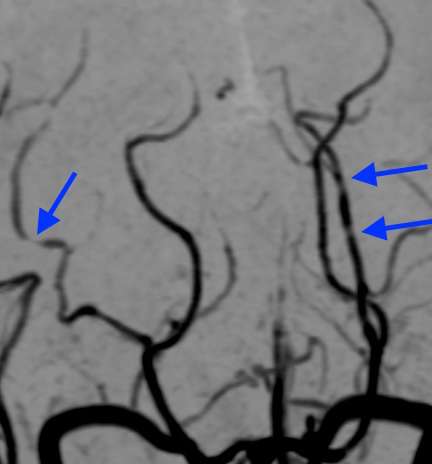

さらに、MRA検査で血管を見たところ、

脳血管の所々に、くびれて細くなった部分が見られています。そして、この画像所見から可逆性脳血管攣縮症候群と診断しました。

この方の場合、脳血管の攣縮以外に明かな異常はありませんでした。したがって、可逆性脳血管攣縮症候群に合併したくも膜下出血と考えられます。

可逆性脳血管攣縮症候群にくも膜下出血が合併する割合は、約30〜34%と言われます。1)2)3)

片頭痛とくも膜下出血は、直接的な関係はありません。しかし、片頭痛から可逆性脳血管攣縮症候群に変化してこのようなくも膜下出血を生じる場合があります。